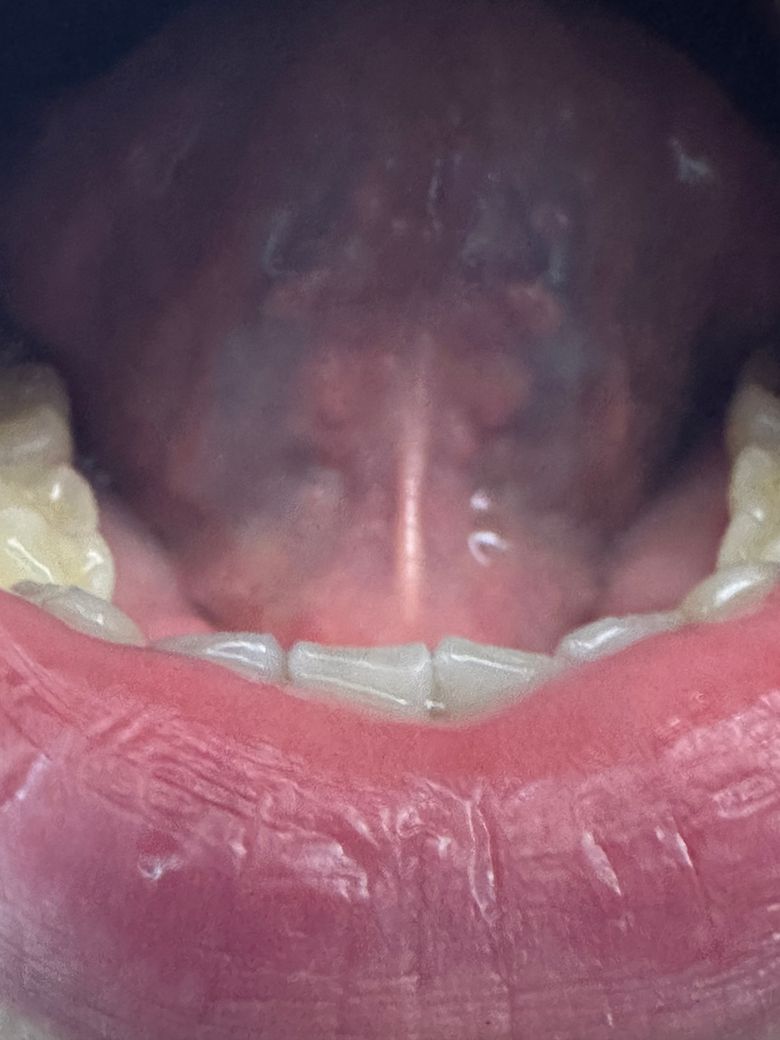

구강 hpv 혀 밑에 돌기들 있는데 맞나요? 후두hpv 인가요? 이빈후과에서 인후염 이라는데 3개월정도 지속 됩니다 hpv 인가요?

구강hpv 혀 밑에 돌기들 있는데 맞나요? 아 그리고 목 인후염이 3개월 정도 가나요? 인후염 후두에 hpv 생기나요? 인후 쫌에 하나염증 하나랑 빨강여즘 여러게 있습니다 또 이빈후과에서 인후염 이라는데

이상해서 올립니다 입안 목에 흰염증 빨강염증 양 옆에 염증들 이 3개월 지속 입니다 목 따가움 가끔 있고 말 많이하면 허스키한 목소리 나옵니다 자세한 답변 해주시면 감사하겠습니다

• 2번 째 사진

이비인후과 진료와 검사를 이미 받아보셨고 그곳에서 인후염이라고 했다면 우선 진단을 빋고 처방 받으신대로 약을 드셔보시는게 맞는 듯 합니다. 후두 유두종을 걱정하고 계신데 사진상으로 보면 진단에 맞는 전형적인 병변은 아닙니다. 이 진단을 백프로 배제하고 싶으시다면 다시 이비인후과 진료 및 검사 받아보셔야 될듯합니다. 감사합니다